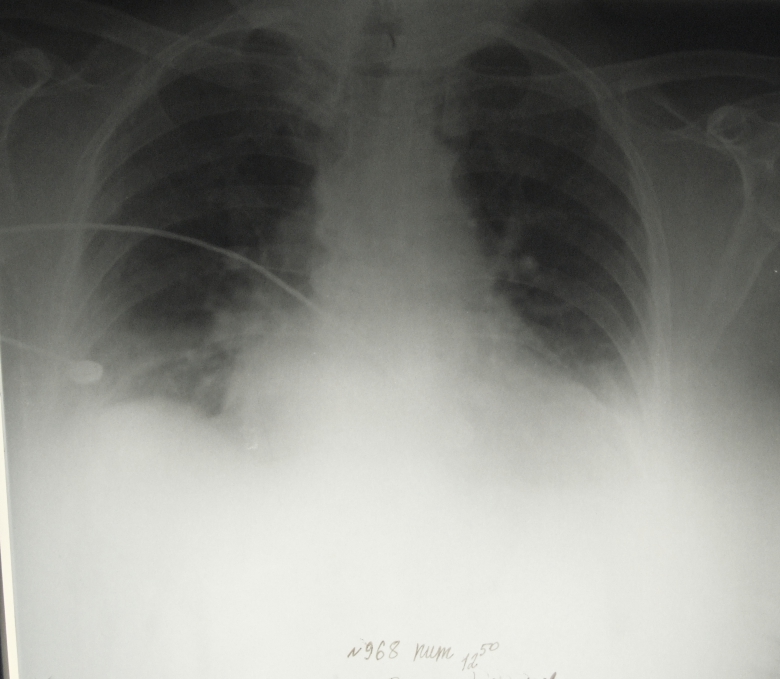

Левая легочная артерия отсутствует полностью. Она окклюзирована! Видны только бронхиальные артерии.

Обсуждалось здесь viewtopic.php?f=24&t=2587